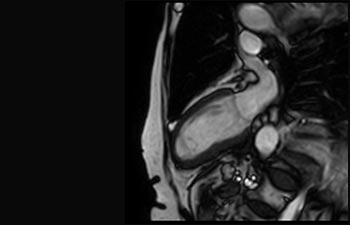

Mayor fiabilidad diagnóstica en neurooncología

Encuentre la aplicación clínica adecuada a sus necesidades